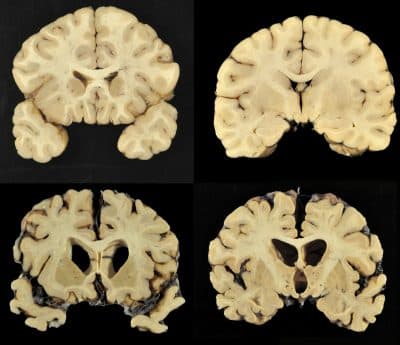

Did Aaron Hernandez Damage Football, Or Was It The Other Way Around?

The stunning news regarding the state of Hernandez's brain complicates his story, writes Steve Almond, just as it should complicate our moral relationship to football.